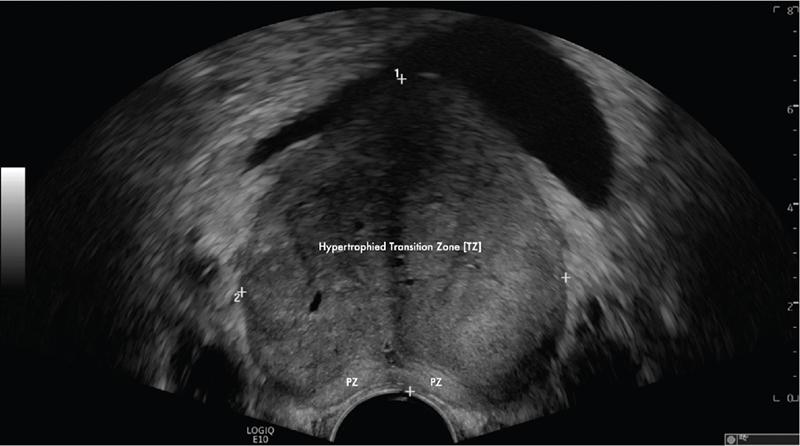

Karthik Ganesan, Disha Lokhandwala, Ujjwal Bhure, Jay Mehta Morphogenesis of the male genitourinary system is governed by the coherent interaction of three units, namely the Wolffian duct, urogenital sinus and foetal gonads. The Wolffian ducts are the embryonic precursors of the male internal genitalia, arising in the anterior intermediate mesoderm at 4 weeks of gestation. They elongate as a cord of cells that caudally extend to the urogenital sinus. Between 5 and 8 weeks of gestation, the urorectal septum divides the cloaca into a ventral compartment, which forms the urogenital sinus, and a dorsal compartment, which forms the rectum. The gonads form as epithelial thickenings on the ventromedial surface of the mesonephros and produce testosterone at 8 weeks of gestation, reaching a peak at 10–15 weeks. Under the effect of testosterone produced by the foetal testis, the prostate anlage forms at the tenth week of gestation. Precursor of the anlage begins with proliferation of solid epithelial buds from the epithelium of the urogenital septum into the adjoining mesenchyme in response to interaction of 5α-dihydrotestosterone with mesenchymal androgen receptors. As growth progresses, solid cords of epithelial cells are formed, growing into the mesenchyme in a specific three-dimensional arrangement (establishes the lobar divisions of the prostate gland). These solid cords develop a central lumen at birth and are lined by a layer of flat basal epithelium and a luminal layer of tall columnar secretory epithelium. Mesenchymal component forms the stroma, which has a large proportion of smooth muscle. Postnatally, the epithelial cords continue to arborize till puberty without any change in volume or glandular architecture. Although the foetal prostate has been described to have a histologically distinct peripheral zone (PZ) as early as 12 weeks of gestation, the mature zonal anatomy develops in concordance with the androgen surge at puberty. The most commonly utilized ultrasonographic technique for the evaluation of the prostate is via a suprapubic approach. The abdominal transducers used in this approach are relatively low frequency and while it offers the advantage of greater depth of penetration without intracavitary probe insertion; however, it does not depict the zonal anatomy and its chief application lies in volume estimation. Hence, transrectal ultrasonography (TRUS) completely outweighs the transabdominal approach in terms of depicting zonal anatomy, visualizing and localizing small lesions, demonstrating vascularity and performing biopsies. TRUS is performed using high frequency transducers (5–7.5 MHz) to optimize soft tissue resolution. An enema is administered 1 h prior to the examination to clear the field of insonation. Patient is positioned in left lateral decubitus, with knees bent toward the chest and ideally a digital rectal examination (DRE) is conducted prior to probe insertion. The transducer is first draped with a sterile barrier and lubricated, After insertion, the barrier is filled with 40–50 cc of water, making sure that no air enters. On completion, water is aspirated and the probe is withdrawn. The gland is initially scanned in the axial plane from the base to the apex, beginning at the level of the seminal vesicles, and the probe is gradually withdrawn to view the entire glandular parenchyma in axial sections up to its caudal aspect. This approach allows a cursory evaluation of glandular symmetry as both halves of the prostate can be evaluated simultaneously. Subsequently, sagittal views are acquired by rotating the probe across the transverse span of the gland, demonstrating the seminal vesicles, midline gland (visualizing both the apex and the base), with sequential scanning up to the contralateral margin of the gland. Sonographically, the prostatic capsule is seen as a smooth well-delineated, hyperechoic structure. With the newer ultrasound systems, the zonal anatomy can be delineated by TRUS; PZ appears echogenic relative to the central zone (CZ) and the transition zone (TZ), which are hypoechoic in juxtaposition (Fig. 11.12.1). Anterolaterally, the preprostatic venous plexuses are seen as anechoic tubular structures with intervening echogenic preprostatic fatty tissue. Glandular volume is estimated using an ellipsoid formula by obtaining the maximum anteroposterior, superoinferior and transverse dimensions and multiplying their product by π/6. Colour Doppler imaging is utilized to illustrate vascularity, as majority of the normal prostatic tissue (excluding the neurovascular bundles [NVBs] and pericapsular and periurethral regions) has symmetrical but sparse flow and an increased microvessel density raises the suspicion of prostatic carcinoma. However, the appearances of prostatic carcinoma can be variable on colour Doppler imaging, ranging from focal increase in vascularity around a nodule to an asymmetric increase in size and number of vessels on the affected side and conventional Doppler has found to elevate specificity by about 5%–10%. Additionally, Doppler imaging has also demonstrated some utility in distinguishing fibrotic tissue from local recurrence. However, vessels supplying cancerous tissue are of the order of 10–50 μm, which is well below the 1-mm resolution limit of conventional Doppler techniques. Contrast-enhanced colour Doppler imaging overcomes this limitation and facilitates imaging of microvessels, using intravenously administered microbubbles (less than 10 μm diameter) of an inert gas (sulphur hexafluoride) with a lipid or galactose shell, allowing quantification of blood flow in the cancerous microvessels. Additionally, these microbubbles act as vascular tracers and by monitoring the passage of a bolus injection through the tissue of interest, time–intensity curves are created. This permits the formulation of functional indices, including bolus arrival time, time to peak intensity, area under the curve and wash-in/wash-out curves. These indices can further extrapolate functional images, on a pixel-by-pixel basis, overlaid on grey-scale images. Quantitative methods to demonstrate perfusion are based on the destruction of microbubbles by high-power ultrasound pulses, and then observing the rate of microbubble replenishment in the field of interest to calculate flow rate. Halpern et al. utilized contrast-enhanced ultrasound and intermittent harmonic imaging with power Doppler, and exhibited an increment in sensitivity from 38% to 65% with a specificity of 80% in prostate cancer detection. Cadence contrast pulse sequencing (CPS) is a low-power multipulse imaging technique utilizing pulses with variable amplitudes and phases followed by a summation of the resulting echoes, permitting tissue suppression, allowing detection of even a small amount of contrast agents retained in the tissues. Real time elastosonography evaluates and quantifies tissue stiffness (Young’s modulus) by measuring strain under an applied stress (transducer compression) and maps areas of variable stiffness in colour-coded and grey-scale images simultaneously and shows potential in improving prostatic carcinoma detection. In a study comparing elastography and T2-weighted (T2-w) endorectal magnetic resonance imaging (MRI), similar sensitivity rates and negative predictive values (NPVs) were attained in the detection of prostatic carcinoma. Prostate gland is an inverted cone-shaped subperitoneal retropubic gland, with its base located rostrally and apex located caudally. The base is attached to the bladder neck and the apex sits on the urogenital diaphragm and abuts the medial surface of the levator ani muscles, namely the pubourethralis portion, which is separated from the inferolateral surfaces of the gland on either side by the prostatic venous plexus. Normal prostate gland measures approximately 4 × 3 × 3 cm, 15–20 g in weight, with a median volume of 11.5 mL (range, 1.6–20.6) in patients between 21 and 25 years and a median volume of 39.6 mL (range, 13–169.8) in patients between 38 and 83 years. The first comprehensive publication describing the anatomical subdivision of the prostate gland was in 1912 by Lowsley, based entirely on the embryonic glandular morphology at a series of gestational age groups. The budding prostatic ducts were seen to proliferate in five distinct clusters from the primitive urogenital sinus, which formed the basis of its lobar subdivision. It was divided into a ventral lobe (anterior to the urethra), two lateral lobes (lateral to the ejaculatory ducts), a posterior lobe (between the ejaculatory ducts) and a middle lobe (above the ejaculatory ducts). This classification had several shortcomings, the foremost being inclusion of only the embryonic prostate during its conception. Frank highlighted these aspects in 1953 and stated that no definite lobar boundaries exist in the adult prostate and further criticized the exclusion of periurethral glands (inner gland), identifying them as the sole site of origin of benign prostatic hyperplasia (BPH). The chief drawback of all research prior to 1968 was the lack of a concrete histological basis to support the seemingly arbitrary subdivision. McNeal was the first to ascertain histological heterogeneity within the glandular tissue and used it as the basis of his well-acclaimed prostatic zonal classification. The zonal anatomy of the prostate gland conceived by McNeal divided the gland into four distinct zones, namely the TZ, PZ, anterior fibromuscular zone (AFMZ) and the CZ (Fig. 11.12.2). McNeal used the plane of the distal urethra to describe the zonal relationships and divide the gland broadly into three parts, namely the base, midgland and the apex (Fig. 11.12.3). The improved understanding of the prostate anatomy coincided with the development of MRI in the late 1980s, which could depict the zonal anatomy, unlike ultrasonography (USG) or computed tomography (CT). Patterns of ductal growth and radiation from the prostatic urethra form the basis of the zonal anatomy of the gland. Ducts arising from the proximal urethral segment grow towards the urinary bladder. Tiny ducts which are confined by the preprostatic sphincter form the small periurethral gland, whereas ducts which develop distal to the lower border of the preprostatic sphincter extend laterally and then anteromedially to form the TZ. Ducts arising from the verumontanum in the vicinity of the ejaculatory duct orifices and are directed towards the base along the course of the ejaculatory ducts form the CZ, whereas ducts which arise from the lateral recess of the posterior urethral wall of the verumontanum and distal urethra radiate laterally to form the PZ and rostrally posterior to the CZ at the base of the gland. PZ is the dominant glandular component of the prostate gland comprising approximately 70% of the glandular tissue. On T2-w images, the normal PZ has a high T2 signal intensity (SI), owing to the abundant ductal and acinar elements with sparsely interwoven smooth muscle, and can broadly divided into three sections as per the sector map in Prostate Imaging Reporting and Data System Version 2.1 (PI-RADS v2.1), namely posterior medial, posterior lateral and anterior sections (Fig. 11.12.4). At the apex, the anterior sections have a horn-like morphology, curving anteromedially, to nearly encircle the urethra and abut the AFMZ. At the midgland level, the PZ comprises the posterior, both lateral and the anterolateral parts of the gland. At the base, the PZ is located posterior and superior to the CZ and TZ. CZ is an ovoid-shaped structure at the base of the gland, comprising approximately 25% of the glandular tissue, with its apex located at the verumontanum, surrounding the ejaculatory ducts. Beyond age 35, volume of the CZ starts to gradually diminish, as well as the CZ is compressed by the enlarged TZ. In the initial MR studies of prostate, the CZ could not be easily delineated from the TZ. Vargas et al. demonstrated in a population with a mean age of 60 years undergoing MR for prostate cancer assessment, the CZ was visible in 81%–84% of patients. Hansford et al. identified the CZ in 92%–93% of patients on T2-w images and 78%–88% of patients on apparent diffusion coefficient (ADC) maps. Histologically, substantial differences exist between the CZ and PZ, which reflect in the differential appearance on T2-w imaging. These differences are probably attributable to the differential origin, as the CZ is derived from the Wolffian duct, and the PZ and TZ are derived from the urogenital sinus. In the CZ, the acini appear larger and more irregular, with numerous epithelial covered ridges or septa project from the walls of the acini into the lumen, forming a characteristic Roman bridge architecture and intraglandular lacuna, with a prominent basal layer, crowded epithelial cells with granular eosinophilic cytoplasm, decreased luminal fluid and compact stroma. PI-RADS v2 has discouraged the use of the term central gland, as it is not reflective of zonal anatomy or reported on pathologic specimens. CZ demonstrates homogeneously low signal on the T2-w images and ADC maps and can, therefore, mimic prostate cancers. CZ is best identified on the coronal plane T2-w images paralleling the plane of the distal urethra, and appears as a symmetric paramedic paired structures surrounding the ejaculatory ducts from the base of the gland to the verumontanum (Fig. 11.12.5). TZ comprises approximately 5% of the glandular tissue of the prostate. On T2-w images, the TZ normally appears as a homogeneously hypointense structure surrounding the proximal urethra at the base and the midgland level; however, it can also demonstrate inconsistent SI, depending on the relative proportion of glandular and stromal elements (Fig. 11.12.6). Glandular hyperplasia produces higher SI (dominance of acinar elements and secretions), while stromal hyperplasia exhibits lower SI (dominance of muscular and fibrous elements). The TZ is easily demarcated from the PZ by a thick homogeneously low T2 signal surgical capsule, which becomes pronounced in BPH. With increasing age, the TZ demonstrates variegated signal on the T2-w images and ADC maps, due to differential growth of the stromal and glandular elements. AFMZ is a nonglandular muscular tissue that drapes the anterior surface of the gland, superiorly blending into the smooth muscles of the bladder neck and inferiorly extending to the prostatic urethra at the glandular apex. AFMZ is comprised of smooth muscles, which blends with the smooth muscle fibres surrounding the urethra, and rostrally merges with the bladder neck and preprostatic sphincter. High smooth muscle content of the AFMZ is responsible for the MR signature, where in it appears markedly hypointense on the T2-w images and ADC maps, and hypoenhances on the multiphase contrast series (Fig. 11.12.7). With the advancing age, temporal reduction in the size of the AFMZ is noted due to the compressive effects of the BPH. Capsule surrounds the prostate gland, anteriorly merging with the AFMZ anteriorly. Two discrete defects are identified in the prostate capsule, at the base of gland where the ejaculatory ducts enter the prostate and at the apex where in the stroma blends with the sphincter. The capsule is perforated along the anterolateral aspect by multiple vessels and nerves. The capsule appears as a thin dark rim surrounding the gland on the T2-w images and may reveal delayed enhancement on the postcontrast images (Fig. 11.12.8). Primary goal of radical prostatectomy (RP) is to achieve oncologic efficacy, both in terms of short-term and long-term clinical outcomes. However, as the majority of prostate cancers have an indolent clinical course, preservation of function in terms of continence and potency is equally important, and the key to this is a keen understanding of the fascial anatomy and neuroanatomy of the prostate gland. Fascial anatomy of the prostate gland is anatomically complex and poorly understood, and a thorough understanding of the interfacial planes is crucial to avoid mechanical or thermal injury to the NVBs. Periprostatic fascia comprises of a condensation of layers of connective tissue that encapsulate the gland and suspend it from anterior pelvic wall via puboprostatic ligaments. Laterally, the visceral and parietal endopelvic fascial layers fuse to form the fascial tendinous arch. Periprostatic fascia covers the prostate gland and capsule, comprises of two fascial layers, including an inner layer (prostatic fascia) and an outer layer (levator ani fascia), with thin interfascial planes separating these fascia from one another and the prostate capsule. Posteriorly, a continuous fascial layer known as Denonvilliers’ fascia covers the prostate and seminal vesicles. Distribution of periprostatic nerves is highly variable, with growing evidence of nerves both along the dorsolateral and ventrolateral surfaces of the prostate gland. Most of the periprostatic nerves are found posterolaterally; however, a significant portion of the nerves are located ventrally as seen by Eichelberg et al. (21.5%–28.5%) and Lee et al. (19.9%–22.8%). Although anatomic studies have confirmed the presence of ventrolateral periprostatic nerves, the exact clinical importance and functionality of these nerve fibres has not been proven. The cavernous nerves are situated posterolaterally and are the basis of nerve-sparing RP procedure proposed by Walsh and Donker. Unlike the initial theory of Walsh and Donker, few papers have proposed that the nerves are diffusely scattered along the surface of the gland in the form of a curtain or spray-like arrangement without clear bundle formation. Kourambas et al. assessed the precise relationship of the NVBs and cavernous nerves to Denonvilliers’ fascia and proposed that the nerves were not restricted posterolaterally, but were rather diffusely scattered within the fascia extending up to the midline (Lunacek et al., Takenaka et al.). On the basis of more diffuse arrangement of the periprostatic nerves, surgical techniques have been modified, resulting in a more anterior dissection called the ‘curtain dissection technique’ or alternatively a ‘superveil’ technique to preserve the NVBs within the lateral prostatic fascia. The NVB lies within areolar connective tissue surrounding the gland, which separates the capsule from the periprostatic fascia and provides a plane of dissection during nerve-sparing prostatectomy. Prostate gland is supplied and drained by periprostatic vessels, which also supply and drain the penis. Arterial supply of the gland is highly variable and is typically from branches of the internal pudendal artery, which course inferior to the gland prior to supplying the penile cavernosal tissue. Off late, these vessels have gained prominence in radiation-induced erectile dysfunction (ED) (potential vasculopathy), which have led to the development of newer vessel-sparing radiotherapy techniques. Further, with the advent of prostate arterial embolization in benign prostatic hypertrophy (BPH), the vascular supply of the gland is becoming increasingly vital to understand. Gland drains into the obturator, internal iliac, external iliac, common iliac and presacral lymph nodes. Dorsal venous complex is identified immediately ventral to the gland and also drains the penis. Periprostatic nodes are uncommon, are usually discovered near the base of the gland, and are only occasionally seen on MRI. Urethra is the principal anatomic reference point in the prostate gland. Urethra can be divided into a proximal segment and a distal segment, the point of differentiation being located at the verumontanum wherein the urethra makes an approximately 35-degree angulation. The angulation is highly variable and is further affected by the growth of the TZ. On MRI, the distal segment is more conspicuous vis-à-vis the proximal segment and appears a hyperintense core surrounded by a low signal rim on T2-w images. Preprostatic sphincter encases the proximal urethra from the base of the gland to the base of the verumontanum and merges with the AFMZ anteriorly. Verumontanum appears hyperintense on the T2-w images, lies within the distal urethral segment, beyond which the distal urethral segment is partially encircled by striated muscles which blend with the external sphincter beyond the apex of the gland. External sphincter is located distal to the apex is incomplete posteriorly and is anchored into the PZ and surrounds the membranous urethra. Damage to the external sphincter during RP or transurethral resection of the prostate (TURP) may lead to urinary incontinence. Seminal vesicles are paired structures identified posterosuperior to the base of the prostate gland, which appear as convoluted fluid-filled structures. Due to the high fluid content within the normal seminal vesicles, these structures appear as paired structures with intermediate signal walls surrounding a hyperintense core on T2-w images (Fig. 11.12.9). Vas deferens are paired structures located rostral to the base of the gland and anteromedial to the seminal vesicles and appear as cord-like structures with variable signal on the T2-w images. Duct of the seminal vesicle and vas deferens unite in the posterior aspect of the base of the gland to form the ejaculatory duct, which courses caudally to the verumontanum along the plane of the distal urethra, and drain into the orifices in the midconvexity of the verumontanum. Prostate-specific antigen (PSA) is a serine protease, secreted by epithelial cells of the prostate gland and has been found in normal, benign and malignant prostatic tissues. Traces of PSA have also been isolated from endometrial tissue, breast tissue, adrenal neoplasms and renal cell carcinomas; however, for all clinical purposes, PSA is considered as an organ-specific biomarker. Papsidero first demonstrated and quantified serum PSA, which steered the epoch of prostate cancer screening and early detection of prostatic carcinoma. Subsequent studies showed that PSA screening often led to overdiagnosis of low-grade prostate cancers, with no survival difference between the PSA screened and nonscreened groups. Additionally, PSA levels were found to be elevated in a spectrum of prostatic pathologies apart from carcinoma, including prostatitis and benign hyperplasia. The likelihood of overdiagnosis coupled with the lack of specificity set grounds for the longstanding PSA controversy. Did the benefits of screening outweigh the risks of overtreatment? To elevate the specificity of serum PSA testing, a plethora of indices were devised, including free PSA and total PSA, free-to-total PSA (f/t PSA) ratio, age-specific PSA, PSA velocity (PSA-V) and PSA density (PSAD). Serum PSA exists in three forms; the major form (approximately 75%) is bound to alpha-1-antichymotrypsin, followed by free PSA (constituting 5%–50% of serum PSA). The third form (PSA bound to alpha-2-macroglobulin) is not clinically relevant and cannot be detected by any commercial test. A study by Stenman et al. established that a higher proportion of bound PSA and hence a lower ratio of f/t PSA is associated with prostate cancer. Conversely, free PSA can be utilized during follow-up for men with an initial negative biopsy result, wherein declining free PSA with a persistently elevated total PSA would raise suspicion of a neoplastic aetiology. As per the ACS guidelines (Table 11.12.1) for early detection of prostate cancer, men with a 10-year life expectancy or higher should have the opportunity to make an informed (regarding benefits, risks and uncertainties associated with PSA screening) decision for serum PSA testing, with or without DRE. For those who choose to undergo PSA screening, subsequent screening interval is determined on the basis of baseline PSA value. For values below 2.5 ng/mL, screening interval can be extended to 2 years and for PSA between 2.5 ng/mL and 4 ng/mL, an individualized approach is adopted following risk assessment to recommend either further referral or screening on a yearly basis. A PSA level of 4 ng/mL or higher warrants referral for further evaluation or biopsy, for men at average risk for prostate cancer. Although age-specific PSA (Table 11.12.2) is not a component of the ACS guidelines, it is considered as a beneficial parameter in determining the need for biopsy. As there is an expected rise in PSA values with age, setting a lower cut-off value for younger men would increase the sensitivity of detecting organ confined cancers and a higher value in older men would increase specificity. aThere is no proven rationale for using a single PSA-V threshold value. PSA screening guidelines for treated localized prostate cancers are variable and the definition of biochemical (PSA) recurrence remains debatable. Due to this inconsistency, the Prostate Cancer Guidelines Update Panel recommended a standard definition for biochemical recurrence (BCR) after RP and set a cut-off serum PSA (acquired between 6 weeks and 3 months of surgery) of 0.2 ng/mL or greater, along with a second confirmatory PSA. While there is a significant fall in PSA values after RP and a single raised PSA is sufficient to raise suspicion of recurrence, postradiotherapy recurrence requires a rising trend rather than a single cut-off value. The ASTRO Consensus Panel defined postradiotherapy prostate cancer recurrence as three consecutive raises in PSA values after a baseline has been reached. A hiatus in this definition was that no specific time interval between consecutive increases in PSA was determined. In addition to its utility as a screening tool, PSA is also a good prognosticator when used in conjunction with biopsy Gleason score and clinical T-stage, and several pretreatment prostate cancer risk stratification systems are based on these indices. D’Amico et al. proposed a three-group risk stratification system in 1998, which categorized nonmetastatic (M0) carcinomas as low risk, intermediate risk and high risk. Low-risk prostate cancer was defined as 1992 AJCC T1/T2a, PSA ≤10 ng/mL and Gleason score ≤6. Intermediate-risk prostate cancer was defined as 1992 AJCC T2b, and/or PSA 10–20 ng/mL and/or Gleason 7 disease. High-risk disease included any one of the following: 1992 AJCC ≥T2c, PSA >20 ng/mL or Gleason 8–10 disease. In 2001, the GUROC published the results of a consensus meeting which categorized the groups as follows: low risk – 1997 AJCC T1–T2a, PSA ≤10 ng/mL and Gleason ≤6; intermediate risk – 1997 AJCC T1–T2, PSA ≤20 ng/mL and Gleason ≤7 not otherwise low risk and high risk – 1997 AJCC T3–T4 or PSA >20 ng/mL or Gleason 8–10. In due course, newer classification systems have been developed (Table 11.12.3), including the National Comprehensive Cancer Network (NCCN, USA), National Institute for Health and Clinical Excellence (NICE, UK), European Society of Medical Oncology (ESMO), American Urological Association (AUA) and the European Association of Urology (EAU). The NCCN guidelines also incorporate very low-risk (T1c, and Gleason score ≤6, PSA ≤10 ng/mL, <3 positive biopsy cores each ≤50% involved and PSAD of <0.15 ng/mL/g) and very high-risk (T3b–T4) categories. AUA, American Urological Association; EAU, European Association of Urology; GUROC, Genitourinary Radiation Oncologists of Canada; NICE, National Institute for Health and Clinical Excellence; CAPSURE, Cancer of the Prostate Strategic Urologic Research Endeavour; NCCN, National Comprehensive Cancer Network; ESMO, European Association of Urology; T, T-stage; GS, Gleason score; PSA, prostate-specific antigen. Note: Use of the 1997 TNM staging system (T2a one lobe involvement, T2b two lobes involvement, no T2c category). PSA, DRE and TRUS form the diagnostic triad for prostatic carcinoma. It has been well established that manipulations of the prostate gland, including prostatic massage, cystoscopy and perineal biopsy cause a potential increase in serum PSA levels. This raised the question of TRUS affecting PSA levels and it was found to cause a very small rise in PSA only in patients with prostatitis. The effect of DRE on serum PSA levels is also controversial, while some studies found a transient increase in PSA, others found no significant rise in PSA levels after DRE. Therefore, it is advisable to obtain blood samples for PSA testing either prior to DRE and TRUS or after at least 7 days. PSA-V refers to the change in PSA over time using serial measurements. Ideally, at least three consecutive measurements over at least 18–24 months should be used. Carter et al. first defined PSA-V and found that a value of 0.75 ng/mL per year or greater was indicative of carcinoma with a high sensitivity and specificity. Consequently, several studies disproved a definite relationship between PSA-V and prostate cancer, stating that there was no rationale behind a single threshold value for PSA-V. Further, it was found that calculating PSA-V was arduous and while elevated PSA values on serial examinations should raise alarm, there was no added benefit of formally calculating PSA-V. As per NCCN guidelines, the PSA-V cut-off should be based on the initial PSA value with a PSA-V of 0.35 ng/mL/y, when the PSA is ≤2.5 ng/mL and 0.75 ng/mL/y, when the PSA is 4–10 ng/mL PSAD was developed in order to correlate prostate volume and PSA values. The basis of PSAD was that cancer cells produce more PSA per unit volume than normal cells. It is calculated as PSA value divided by the prostate volume as determined by TRUS. This reliance on TRUS leads to interobserver variability and hence PSAD values would differ with the performing sonologist. The chief utility of PSAD is in the diagnostic grey zone of PSA values between 4 and 10 ng/mL and the most commonly used cut-off value is 0.15 ng/mL/cc. However, more recent studies have shown that a value of 0.08 ng/mL/cc has an NPV of 95% in predicting prostate cancer. Additionally, PSAD in conjunction with MRI (PI-RADS score) has proved to be a reliable prognosticator for Gleason score upgrading. The most significant application being avoiding unnecessary biopsies as PI-RADS scores of 1–3 along with PSAD values <0.15 ng/mL/cc showed no Gleason score upgrading on repeat biopsies. In summary, most guidelines recommend shared decision-making for screening of prostate cancer. Limited testing should be conducted in men with low PSA values and a lower life expectancy. The aim should be to overcome challenges posed by the inherent nonspecific nature of serum PSA and reduce superfluous testing, unwarranted biopsies and overdiagnosis. Reliance on parameters like PSA-V that do not have a proven scientific basis is avoidable. Whereas applications of PSA like PSAD along with MRI can greatly reduce patient burden by avoiding follow-up biopsies. Lastly, PSA has no role in assignment of a PI-RADS category, which is based on multiparametric MRI (mpMRI) findings alone. Several ‘novel biomarkers’ are now being developed which are more specific in detecting high-grade prostatic carcinomas. Other human kallikrein proteins have been identified, as prostate cancer biomarkers, of which, human kallikrein 2 (hK2) has shown a high specificity. While hK2 and PSA have an overlapping primary structure, malignant cells express hK2 to a higher degree than benign epithelial cells, particularly in aggressive cancers. Engrailed-2 (EN2) is an HOX gene family transcription factor seen exclusively in malignant prostate tissue, with a reported sensitivity and specificity of 66% and 88%, respectively. Annexin A3 is a calcium-binding protein measured in urine samples following prostatic massage, potentially reducing unnecessary biopsy in men with a PSA of 2–10 ng/mL. However, extensive prospective evaluation of these biomarkers is necessary to replace PSA testing in clinical practice. Positron emission tomography (PET)/CT has evolved over the last two decades to make a paradigm shift in the field of imaging, moving from morphological imaging to molecular level and completely changing the approach to how we view the disease. Though the main workhorse tracer in the field of PET/CT is 18-fluorine-fluorodeoxyglucose (18F-FDG), it has limitations with regard to prostate cancer, especially in indolent or well-differentiated ones. However, that void has been filled up by the new kid on the block and that is prostate-specific membrane antigen (PSMA)-based radiotracer. PSMA is a type II transmembrane protein with intracellular (19 amino acids), transmembrane (24 amino acids) and extracellular (707 amino acids) domains, which functions biochemically as a glutamate carboxypeptidase. After a ligand binds to PSMA, internalization occurs and it is either retained in lysosomal compartments or released into the cytoplasm. PSMA expression and localization in the normal human prostate is associated with cytoplasm and apical side of the epithelium surrounding prostatic ducts but not basal epithelium and neuroendocrine or stromal cells. Neoplastic transformation of prostate tissue results in the transfer of PSMA from the apical membrane to the luminal surface of the ducts. PSMA is an ideal target for molecular imaging of prostate cancer as its expression is significantly upregulated in prostatic carcinoma cells compared to benign prostatic tissue, in density (100 to 1000 times) as well as activity (8 to 10 times). PSMA expression increases with increase in Gleason score, stage and grade of tumour, with further increased expression with transition to androgen-independent/castration-resistant prostate cancer. PSMA-binding analogues, because of their high sensitivity and specificity, possess precise imaging characteristics required for critical decisions in the management of prostate cancer (PCa). The most commonly used PSMA radiotracer is 68Gallium-PSMA-11, followed by 18F-PSMA. The availability of 18F-labelled PSMA radiopharmaceutical has helped to advance the reach of PSMA PET imaging to wider locations owing to higher available amount of the radiotracer due to its production from a cyclotron, compared to 68Ga-PSMA which is eluted from individual in-house generator. Additional benefit is accrued with excellent image quality owing to optimized radiotracer doses, higher imaging statistics and favourable decay properties of 18F radioisotope. The normal physiological biodistribution of PSMA-based radiotracers is seen in lacrimal and salivary glands, liver, spleen, kidneys and intestine. Physiological activity is also seen in celiac and cervicothoracic ganglia. Unbound PSMA radiotracer is excreted by the kidneys into the urinary bladder. PSMA PET/CT has established roles of varying degrees in the imaging of different aspects of prostate cancer including primary diagnosis, staging, BCR after primary prostate cancer treatment (prostatectomy), identification and significance of oligometastasis, restaging and treatment response assessment and monitoring. PSMA PET/CT is useful at the stage of diagnosis in that subset of patients with tumour-negative biopsy samples, by contributing the useful molecular information to mpMRI, helping to precisely delineate suspicious lesions for targeted biopsies. In intermediate-risk to high-risk primary prostate cancer patients, PSMA-based imaging has shown improvement in detection of metastatic disease compared to the CT and mpMRI, which has led to reduced demand and dependence on additional cross-sectional imaging or bone scintigraphy. Furthermore, PSMA PET/CT has also established its clear advantage over conventional imaging in patients with biochemically recurrent prostate cancer with improved and increased detection of metastatic sites even at low serum PSA values. As it happens in cancer, biopsy is the standard of diagnosis and likewise in PCa, it is the multicore biopsy, which is the gold standard. However, because of its size, location, approach and sensitive and delicate nature, yield and accuracy can often be restricted, especially in inexperienced hands. The diagnostic yield of biopsy can go down as low as 40% and false negative (FN) rate can climb as high as 25%–30%. PSMA overexpression follows high-grade PCa cells and increases with Gleason score. In normal prostate tissue, PSMA to PSA ratio is about 1, which decreases in BPH, increases in primary PCa cells, further increases with intratumoural angiogenesis, higher in metastatic lesions than in primary PCa cells and further upregulated in castration-resistant situation. In a study by Litwin and Tan in 2017, the FN rate of multicore biopsy was around 21%–28% and about 15% of the cases were undergraded vis-à-vis final prostatectomy results. While the diagnostic accuracy of random multicore biopsy was around 76.3%, that of 68Ga-PSMA PET/CT was upward in the range of 85.5%. The role of PSMA PET/CT in the primary/initial diagnosis of prostate cancer is generally limited to clinically intermediate-risk to high-risk patients with negative biopsy or reluctance to biopsy or noncooperation or nonfeasibility and for confirmation and staging in clinically high-risk patients. In low-risk patients, metastatic spread is very unlikely and hence it is a relative indication at the time of initial diagnosis in low-risk patients. And, its role in screening is variable and debatable (Fig. 11.12.10). Staging is crucial as it has considerable influence on deciding further line of management and treatment choices, which includes RP, radiotherapy or palliative systemic treatment, deciding on the extent of the pelvic nodal dissection during surgery, planning the radiotherapy field and consideration of multimodal therapy. Accurate staging helps to make the most appropriate choice of treatment modality (Fig. 11.12.11). In a meta-analysis of five studies with histopathology as gold standard, which included 216 patients, the per-lesion sensitivity of 68Ga-PSMA PET/CT ranged from 33% to 92% (33% value being an outlier due to the retrospective analysis based only on the reports, in absence of the images) with higher specificity of 82%–100%. For T-staging, PSMA PET/CT showed a significantly higher tumour detection rate of 92% vis-à-vis 66% with MR alone. In regard with N-staging, the majority of metastatic nodes from prostate cancer are small subcentimetre-sized, less than 8 mm, which are overlooked, missed or inconclusive on morphological imaging (CT and MRI) (falling below size criteria for morphological imaging). Accurate N-staging is important because lymph node involvement is a critical prognostic factor in cancer management, and precise pelvic nodal clearance could be curative and could make a difference in treatment success and long-term outcome in prostate cancer (Fig. 11.12.12). Also, accurate prediction of pelvic nodal metastases may spare nodal dissection, shorten surgical time and in turn help to reduce undesirable complications. In one study from 2016 involving 130 patients with intermediate-risk to high-risk prostate cancer, the metastatic nodal detection rate by 68Ga-PSMA PET was around 66% compared to 44% with MRI. PSMA PET has shown superior predictive value for surgical response over Gleason score, pT stage and PSA (at the time of imaging). In a literature overview by Luiting et al. in 2019 involving 9 retrospective and 2 prospective studies, the specificity of PSMA PET/CT in detection of pelvic nodal metastases before initial treatment reached as high as 80%–100%. PSMA PET/CT increases the confidence level in the evaluation of nodal metastases and an NPV reaching up to 86%. With imaging becoming more precise and adding different modalities together, the question arises about the tiny nodes less than 5 mm size. In a study by van Leeuwen et al. in 2017, the mean size of missed lymph node metastases was 2.7 mm. In a recent study by Ferraro et al. in 2020, about the impact of PSMA PET staging on clinical decision-making in intermediate-risk to high-risk prostate cancer patients, PSMA PET provided new information in 36% of patients and this helped to change treatment decision in nearly 27% of patients, which means in every fourth patient they studied. PSMA PET in combination with CT or MRI can achieve complete and precise Tumor, Nodes and Metastases (TNM) staging including staging of local tumour, nodal assessment and bone and organ/visceral metastases, in one single imaging session, with improved accuracy and better outcome, and in turn leading to precise treatment planning, eventually superseding conventional imaging. Accurate localization of prostate cancer lesions in patients with BCR is a major challenge. Especially at low serum PSA values (as low as less than 0.5 ng/mL), the precise determination of localized disease and metastatic spread is of great importance for further disease management. Conventional imaging modalities including CT scan or bone scintigraphy have limited detection rate for metastatic disease at low serum PSA values in this setting of BCR. PSMA PET/CT imaging plays a very valuable role in the evaluation of BCR (Fig. 11.12.13), which is indeed very critical and important aspect in prostate cancer management. The international consensus on BCR includes PSA >0.2 ng/mL for two times after prostatectomy, or PSA nadir + 2 ng/mL after radiotherapy or brachytherapy. With the incorporation of PSMA PET/CT in the imaging armamentarium, the overall detection rate for local recurrence as well as metastases with BCR after prostatectomy reached up to 90%. The detection rate increases with rising PSA level, jumping over 90% with PSA level going above 1 ng/mL. In a homogeneous consecutive cohort of 248 patients with BCR after RP with mean serum PSA value of 1.99 ng/mL, studied by Eiber et al., 68Ga-PSMA PET/CT showed detection rates of 57.9%, 72.7%, 93.0% and 96.8% for patients with serum PSA values of 0.2–<0.5 ng/mL, 0.5–<1 ng/mL, 1–<2 ng/mL and ≥2 ng/mL, respectively. Tumour Gleason score or androgen deprivation therapy (ADT) did not significantly influence the detection rates (Fig. 11.12.14). These detection rates for 68Ga-PSMA PET are substantially higher than those reported for choline-based PET radiotracers, which fell between 19% and 36% at serum PSA levels of <1.5 ng/mL. The improved detection rates are due to the incremental value of molecular imaging as 68Ga-PSMA PET exclusively showed findings not evident on diagnostic CT in 32.7% of patients with information about additional involvement of different anatomical region in 24.6%. A high PSA-V and short PSA doubling time showed a tendency towards increased detection rates, though not statistically significant. As salvage radiotherapy is most effective at low serum PSA values, optimized radiotherapy planning with precise definition of target volume for concerned lesions for appropriate boost radiotherapy can be achieved with the help of PSMA PET/CT imaging. Lesion detection rate with PSMA PET/CT in the setting of BCR: PSMA PET/CT imaging helps to identify patients with oligometastatic disease who are suitable for salvage therapy with PSMA-radioguided surgery. PSMA radioligands, by the virtue of their high sensitivity and specificity, can be used for intraoperative tracking of even small metastatic prostate cancer lesions that can be well localized and subsequently removed using this radioguided surgery for salvage procedures. Identification and treatment of oligometastatic disease (3 to 5 positive sites) with targeted therapies such as surgery or radiotherapy may allow deferral of systemic therapies such as ADT, thereby delaying and reducing potential morbidity associated with systemic salvage therapy. The fusion of PSMA PET and MRI, instead of CT, may improve detection rates further in patients with very low serum PSA values (<0.5 ng/mL). The addition of mpMRI to PET can improve the diagnostic accuracy because of the higher soft tissue resolution and detection efficacy of mpMRI for local recurrence compared to CT. Advantages of PET/MRI include excellent anatomical and zonal resolution of the prostate gland with T2-w sequences, and additional useful information about suspicious lesions from functional MRI sequences like diffusion-weighted images (DWI) and dynamic contrast-enhanced (DCE) imaging. Early and accurate detection of tumour burden helps to plan further management strategy including salvage pelvic radiotherapy or salvage nodal dissection and eventually improve the prognosis. PSMA PET/CT also plays an important role in mapping the overall tumour burden, and separating oligometastatic disease from multiple metastases (Fig. 11.12.15). PSMA PET/CT also plays an important role in monitoring the treatment efficacy as well. 99mTc-methylene diphosphonate (99m Tc-MDP) (gamma camera-based radiotracer – single-photon emission computerized tomography (SPECT)/CT) or 18F-sodium fluoride (NaF) (PET/CT-based radiotracer) are bone-specific biomarker of osteoblastic activity. 18F-NaF has superior diagnostic performance compared to 99mTc-MDP (phosphonates) bone scintigraphy in detection of bone metastases, because of different radiotracer characteristics (different energy levels) and different scanners (PET/CT scanners vs conventional gamma scanner) leading to better resolution and clarity with 18F-NaF PET/CT scans. NCCN recommends bone scintigraphy in patients with PSA levels of more than 20 ng/mL or patients with T2 disease with PSA levels more than 10 ng/mL. However, their routine use in clinical practice is limited by relative lack of sensitivity and specificity vis-à-vis PSMA PET/CT and also not able to assess soft tissue lesions, which is possible with PSMA PET/CT (Fig. 11.12.16). Bone scans often fail to detect a lesion when PSA is less than 10 ng/mL in the setting of PSA recurrence post-RP, whereas PSMA PET/CT has been sensitive in the detection of lesions even at the PSA level of less than 0.5 ng/mL. Prostate cancer is a leading cause of cancer-related death in men; however, many patients with the prostate cancer do die of other causes. Hence, it is of paramount clinical importance to accurately risk stratify patients, to distinguish those with low risk to intermediate risk who could be managed conservatively or alternatively those with high risk for morbidity and mortality who would benefit from an aggressive line of therapy. Detection, risk stratification, staging, individual centred management, monitoring and surveillance of prostate cancer have undergone substantial evolution with time. MRI of the prostate gland was first described by Hricak et al. in 1983 and for long was used for staging patients with biopsy-proven prostate cancer and also occasionally served as a problem-solving tool. With recent advancements in MR technology, multiparametric imaging has become the cornerstone of the prostate cancer management, aiding in detection, characterization, risk stratification, biopsy guidance, surveillance and monitoring. This has been further enhanced and strengthened with the introduction of PI-RADS v2.0 in 2015 which helped standardize communication between the radiologists and urologists, and aided in the clinical decision-making process. As the role of MRI has expanded from detection to surveillance and monitoring, the entire clinical context needs to be available to the radiologist prior to performing an mpMR in order to optimize reporting. Both the imaging techniques and its interpretation may vary with the clinical context. In patients with no prior history of therapy, both T2-w images and DWI have a greater impact on reporting and interpretation, whereas in patients with prior therapy T1-w DCE imaging plays a more critical role in interpretation. In routine clinical practice, PI-RADS v2 recommends that PSA levels, detailed results of prior prostate biopsies and therapies be available to the radiologist at the time of performing and interpreting MR findings. Postbiopsy intraglandular haemorrhage occurs after image-guided prostate biopsies and is a confounder, which may obscure an underlying cancer. The greater extent of haemorrhage is attributable to the production of citrate within the prostate gland, which acts as an anticoagulant. The rate at which haemorrhage resolves is highly variable, often fully resolving in a shorter period in some patients and alternatively persisting for many months. Haemorrhage exclusion sign is a useful imaging finding, which may allow the radiologist to localize prostate cancer, as cancerous tissue has low levels of citrate and hence the propensity to haemorrhage in cancerous tissue is lower vis-à-vis benign glandular tissue. In addition, postbiopsy haemorrhage produces milder hypointensity on the T2-w and ADC maps vis-à-vis cancerous tissue. Ideally, a timeframe of 6–8 weeks has been suggested between the biopsy and the mpMRI. However, in routine clinical practice, the need to accommodate patients immediately postbiopsy or within a shorter time frame does exist, as the information provided by mpMR does overweigh the impact on haemorrhage on intraglandular tumour detection. Rectal over distension with faecal matter or gas impairs the quality of prostate mpMRI and especially seems to exacerbate artefacts on DWI. These issues seem to impact imaging with phased array coil rather than endorectal examinations. To avoid these artefacts, patients may be instructed to evacuate shortly before the examination, use a laxative or minimal enema prior to the procedure, have a preparatory enema or use antispasmodic agents to reduce potential artefacts from bowel peristalsis. Though various approaches do exist to adequately empty the rectum and minimize the artefacts, there is a lack of consensus on the optimum technique. mpMRI of the prostate gland can be performed on a 1.5 Tesla (1.5 T) or a 3 Tesla (3 T) scanner. Vastly improved signal-to-noise ratio (SNR) is the critical advantage of a 3 T scanner over a 1.5 T scanner, which in terms of prostate imaging translates into acquisition of high quality images with improved spatial and temporal resolutions, and also acquisition of higher quality functional sequences for quantitative imaging. Therefore, increasing field strength results in better detection and characterization of prostate cancer. On the contrary, higher field strength can amplify susceptibility artefacts arising from rectal air or metallic prosthesis. Other than field strength, many factors impact image quality and resolution including scanner model, gradient quality, slew rate, coil architecture and design and the sequence MR acquisition parameters. Prostate examinations are performed using a phased array coil placed over the pelvis. In certain institutions, an additional endorectal coil may also be used to achieve a higher SNR which improve the visualization of the prostate capsule and NVBs. Utilization of endorectal coils has certain drawbacks and results in patient discomfort, increased cost and scan duration and causes gland distortion. Endorectal coils improve imaging quality and local staging; however, with recent advances in coil technologies, phased array surface coils do provide similar high quality resolution images, which allows for accurate local staging. Currently, PI-RADS v2.0 does not insist on the use of endorectal coil and allows radiological practices to select hardware and optimize sequences that are most appropriate for the given clinical setting. mpMRI of the prostate gland is a combination of anatomical (morphological) and functional sequences. As per the PI-RADS v2 guidelines, the key sequences recommended include triplanar high-resolution axial T2-w images, high b-value axial DWI and ADC map and axial T1-weighted (T1-w) DCE images. High-resolution axial T2-w images and DWI are used to initially localize the ‘index lesion’ in the prostate gland. High-resolution sagittal and coronal T2-w images aid in colocalization of the ‘index lesion’ in terms of its spatial relationship with the gland. High-resolution T2-w images are the principal sequences of mpMR and are acquired with a small field-of-view (120–140 mm) in sagittal, oblique axial and oblique coronal planes. The high-resolution oblique axial and oblique coronal T2-w images are acquired orthogonal and parallel to the long axis of the prostatic urethra. These anatomical images provide exquisite demonstration of prostatic zonal anatomy, prostate capsule and periprostatic structures, which allows to accurately detect extraprostatic extension. An alternative to the acquisition of three separate T2-w sequences is the acquisition of a single volumetric 3-D T2-w imaging sequence with small near-isotropic voxels, which can then be retrospectively reconstructed in any plane. However, few concerns regarding the 3-D acquisition exist, including long acquisition time that may predispose to greater motion artefacts, reduced in-plane resolution and superimposed T2 and T1 contrast, which may diminish lesion conspicuity. PZ: Normal PZ has high SI on the T2-w images due to its high water content. Most prostate cancers exhibit low SI on T2-w images; however, mucinous adenocarcinomas may have a predominantly high SI. Low SI in the PZ may appear focal or diffuse and is not sine qua non for cancer, and may be seen in chronic prostatitis, glandular atrophy, postbiopsy haemorrhage or represent posttreatment sequelae. Rosenkrantz et al. demonstrated a diagnostic accuracy of 60% for T2-w imaging and showed that T2-w images is only moderately accurate for the detection of cancer and is not adequate for the diagnosis and localization of prostate cancer. T2-w images exquisitely demonstrate important morphological features of the lesion, which may aid in differentiation of cancerous tissue from its benign mimics, including size, shape and margin. Morphological features may overlap between benign lesions and low-risk to intermediate-risk cancers, but are very conspicuous in high-risk cancers. Benign lesions tend to appear linear-shaped or wedge-shaped and have indistinct margins, whereas prostate cancer appears as focal, crescentic or lentiform-shaped lesions. Lesion size is also a predictor for benign versus malignant, with larger lesions more likely to represent prostate cancer with a greater propensity to develop extracapsular extension. T2-w imaging is not the dominant sequence used to assess lesions in the PZ. T2-w PI-RADS v2 categories for PZ lesions are based on the SI, size, shape and margin of the lesion. PI-RADS category 1 is assigned to a homogeneously high SI normal PZ. PI-RADS category 2 lesions are linear-shaped or wedge-shaped, or present as areas of mildly low SI with indistinct borders. PI-RADS category 3 lesions have moderately low SI, but are heterogeneous or noncircumscribed are considered indeterminate. PI-RADS category 4 lesions have a high probability for clinically significant prostate cancer, are focal mass-like, circumscribed, exhibit homogeneously moderate to marked low SI and are less than 1.5 cm in size and do not exhibit extracapsular extension. PI-RADS category 5 lesions have a high probability for clinically significant prostate cancer, are focal mass-like, circumscribed, exhibit homogeneously moderate to marked low SI, are greater than or equal to 1.5 cm in size and/or exhibit extracapsular extension. Findings of extraprostatic extension (EPE) include focal capsular bulge with whiskering of the periprostatic fat, capsular irregularity, NVB asymmetry, obliteration of rectoprostatic angle and seminal vesicle invasion (SVI). TZ: Accurate detection and characterization of focal lesions in the TZ is the greatest challenge in the assessment of mpMRI. The challenge is most profound in middle age and elderly patients, the same population subset at risk for developing prostate cancer. T2-w imaging is not the dominant sequence used to assess lesions in the PZ. T2-w imaging is the dominant sequence used to assess lesions in the TZ in view of its ability to assess lesion texture and margins. BPH affects the periurethral TZ and glandular tissue and is characterized by the development of multiple variable size encapsulated nodules exhibiting variegated T2 signal due to the differential proportions of stromal hyperplasia and glandular hyperplasia, termed as organized chaos. Stroma rich BPH nodules pose a serious diagnostic challenge as this entity appears as low SI on T2-w images and hence lesion morphology plays a pivotal role in distinguishing this entity from prostate cancer. PI-RADS category 1 is assigned to a homogeneously intermediate SI normal TZ (Fig. 11.12.17). PI-RADS category 2 lesions are well-circumscribed and encapsulated nodules with low or heterogeneous T2 SI and are typically benign (Figs. 11.12.18 and 11.12.19). PI-RADS category 3 lesions are considered indeterminate, exhibit heterogeneous SI with obscured margins and are of any size (Fig. 11.12.20). PI-RADS category 4 lesions have a high probability for clinically significant prostate cancer, are lenticular or indistinct foci of homogenous moderately low SI, are less than 1.5 cm in size and do not exhibit extracapsular extension (Fig. 11.12.21). PI-RADS category 5 lesions have a high probability for clinically significant prostate cancer, are lenticular or indistinct foci of homogenous moderately low SI, are greater than or equal to 1.5 cm in size and/or exhibit extracapsular extension (Fig. 11.12.22).